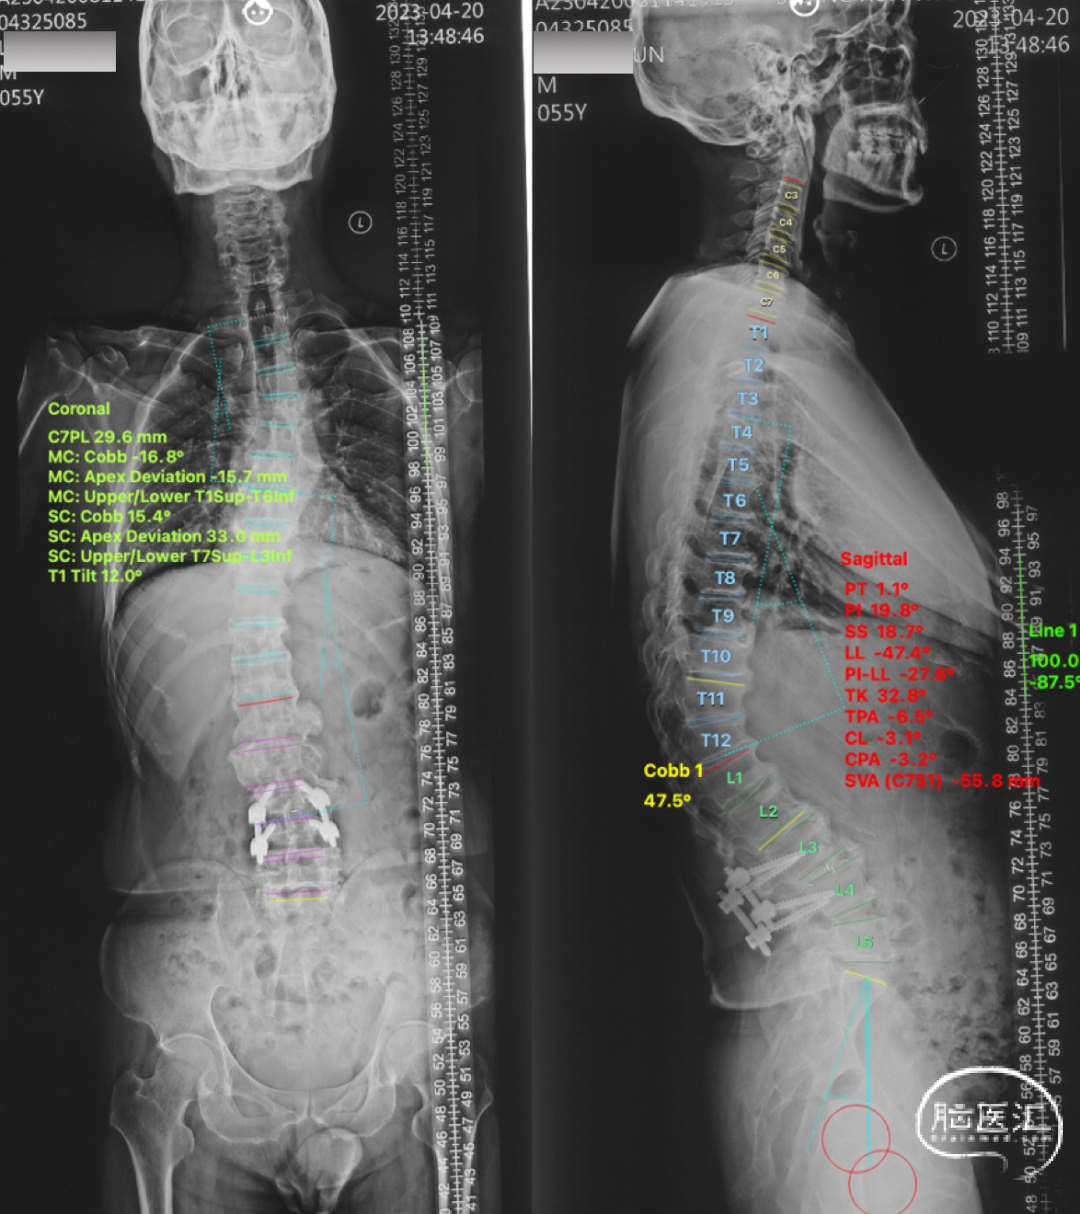

本次术前脊柱全长片

🔺SVA -55.8mm,TK 32.8°,Cobb 15.4°,C7PL 29.6mm